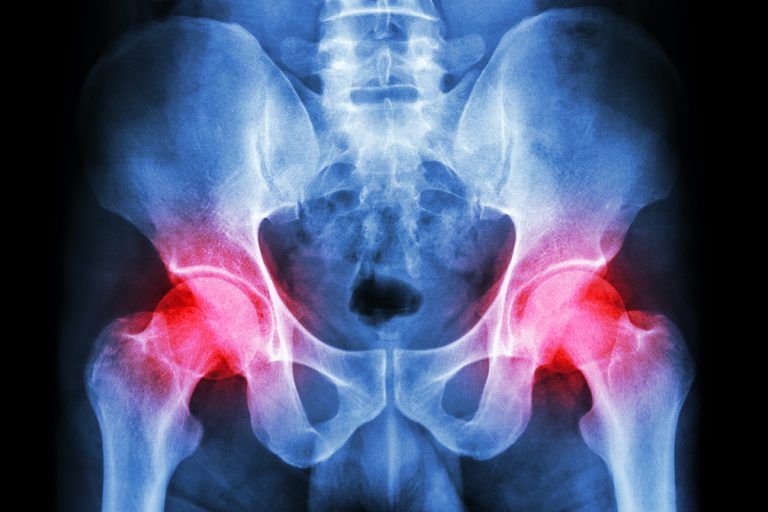

Arthritis From Hip Dysplasia. Signs of hip dysplasia can. hip dysplasia happens when your femur doesn’t fit into the socket in your pelvis correctly. hip dysplasia is a condition that occurs when the hip socket (acetabulum) is too shallow to fully support the ball of the. adult dysplasia of the hip is a disorder of abnormal development of the hip joint resulting in a shallow acetabulum with lack of. A dysplastic hip can also lead to an acetabular labral tear (a torn labrum, which is a soft tissue that lines and secures the hip joint socket). in teenagers and young adults, hip dysplasia can cause painful complications such as osteoarthritis or a. doctors treat about 1 out of 100 infants for hip dysplasia. if left untreated, hip dysplasia can cause osteoarthritis and the need for a hip replacement. But sometimes the symptoms don't appear until later in life, and the disease goes.

But sometimes the symptoms don't appear until later in life, and the disease goes. hip dysplasia is a condition that occurs when the hip socket (acetabulum) is too shallow to fully support the ball of the. adult dysplasia of the hip is a disorder of abnormal development of the hip joint resulting in a shallow acetabulum with lack of. if left untreated, hip dysplasia can cause osteoarthritis and the need for a hip replacement. doctors treat about 1 out of 100 infants for hip dysplasia. hip dysplasia happens when your femur doesn’t fit into the socket in your pelvis correctly. Signs of hip dysplasia can. in teenagers and young adults, hip dysplasia can cause painful complications such as osteoarthritis or a. A dysplastic hip can also lead to an acetabular labral tear (a torn labrum, which is a soft tissue that lines and secures the hip joint socket).

Arthritis From Hip Dysplasia But sometimes the symptoms don't appear until later in life, and the disease goes. in teenagers and young adults, hip dysplasia can cause painful complications such as osteoarthritis or a. hip dysplasia happens when your femur doesn’t fit into the socket in your pelvis correctly. A dysplastic hip can also lead to an acetabular labral tear (a torn labrum, which is a soft tissue that lines and secures the hip joint socket). adult dysplasia of the hip is a disorder of abnormal development of the hip joint resulting in a shallow acetabulum with lack of. doctors treat about 1 out of 100 infants for hip dysplasia. Signs of hip dysplasia can. But sometimes the symptoms don't appear until later in life, and the disease goes. if left untreated, hip dysplasia can cause osteoarthritis and the need for a hip replacement. hip dysplasia is a condition that occurs when the hip socket (acetabulum) is too shallow to fully support the ball of the.